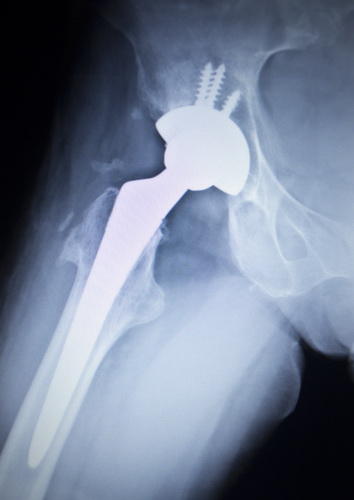

- Установка эндопротеза. В верхней части бедренной кости устанавливается металлический стержень, к которому крепится головка, после этого фиксируются вкладыш и чашка протеза.